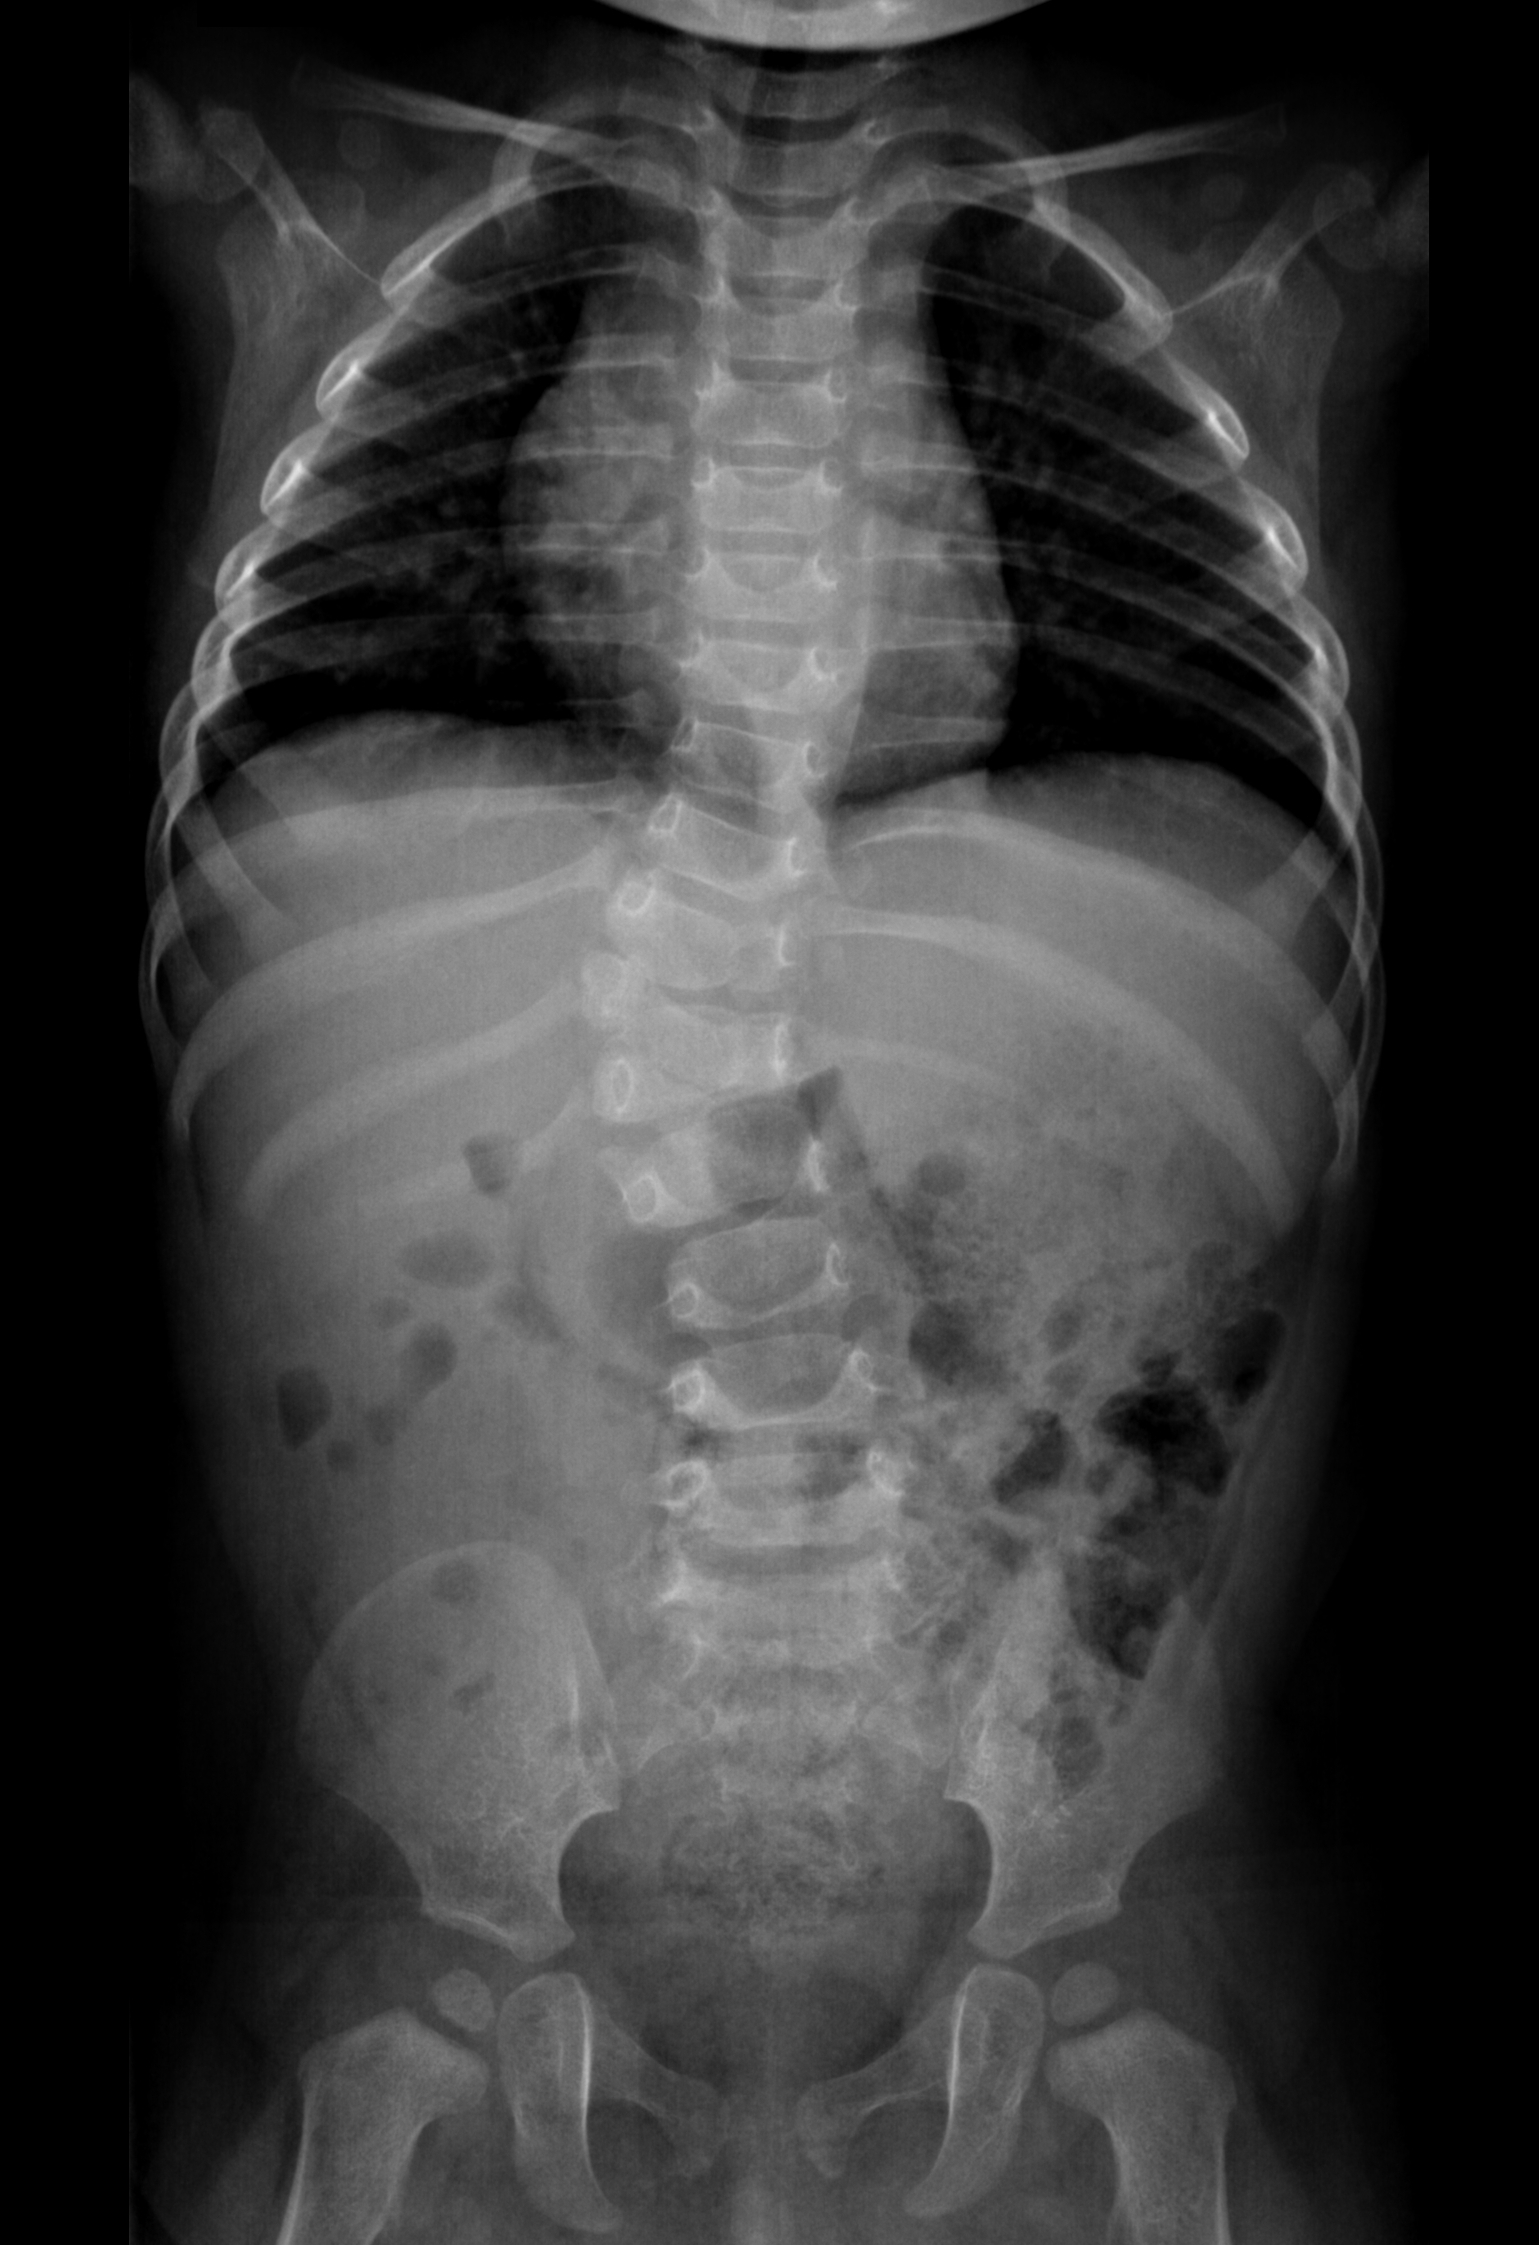

La scoliosi infantile compare entro i primi 3 anni, spesso ancora prima della deambulazione. È rara — circa l’1–2% dei casi totali — ma più frequente nei maschi.

È necessario intervenire con una diagnosi accurata, perché si può arrivare a curve di 80°-100° che vanno trattate il prima possibile. Se è vero che solitamente scoliosi così aggressive finiscono per essere operate, esistono anche in letteratura casi di risoluzione spontanea.